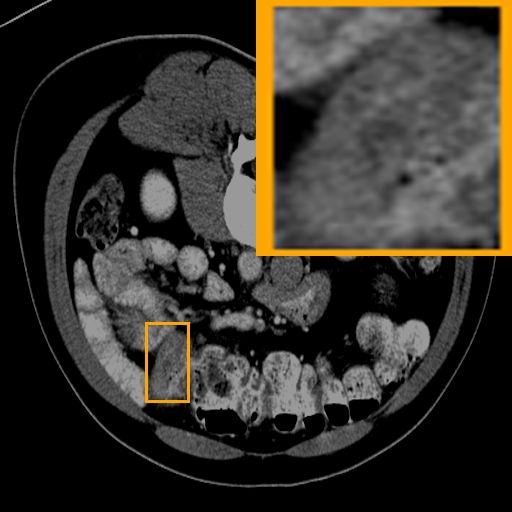

Figure 3: Qualitative comparison visualization of DEAP-3DSAM and baselines on four datasets.

IV-B2 Qualitative Performance Comparison

We also performed qualitative analysis on four datasets. As illustrated in Fig. 3, DEAP-3DSAM accurately identifies the target regions and closely matches their size. In contrast, 3DSAM-Adapter [3dsamadapter] exhibits limitations in matching the size and shape of the target regions. This proves that DEAP-3DSAM captures more complex image features, owing to its Dual Attention Prompter and Feature Enhanced Decoder. Furthermore, while these SAM-based methods are nearly capable of localizing the target regions, many traditional methods, i.e. UNETR++ [unetr++], Swin-UNETR [swinunetr], and TransBTS [transbts], struggle to achieve this. This highlights the potential of SAM-based methods for addressing complex 3D segmentation tasks.